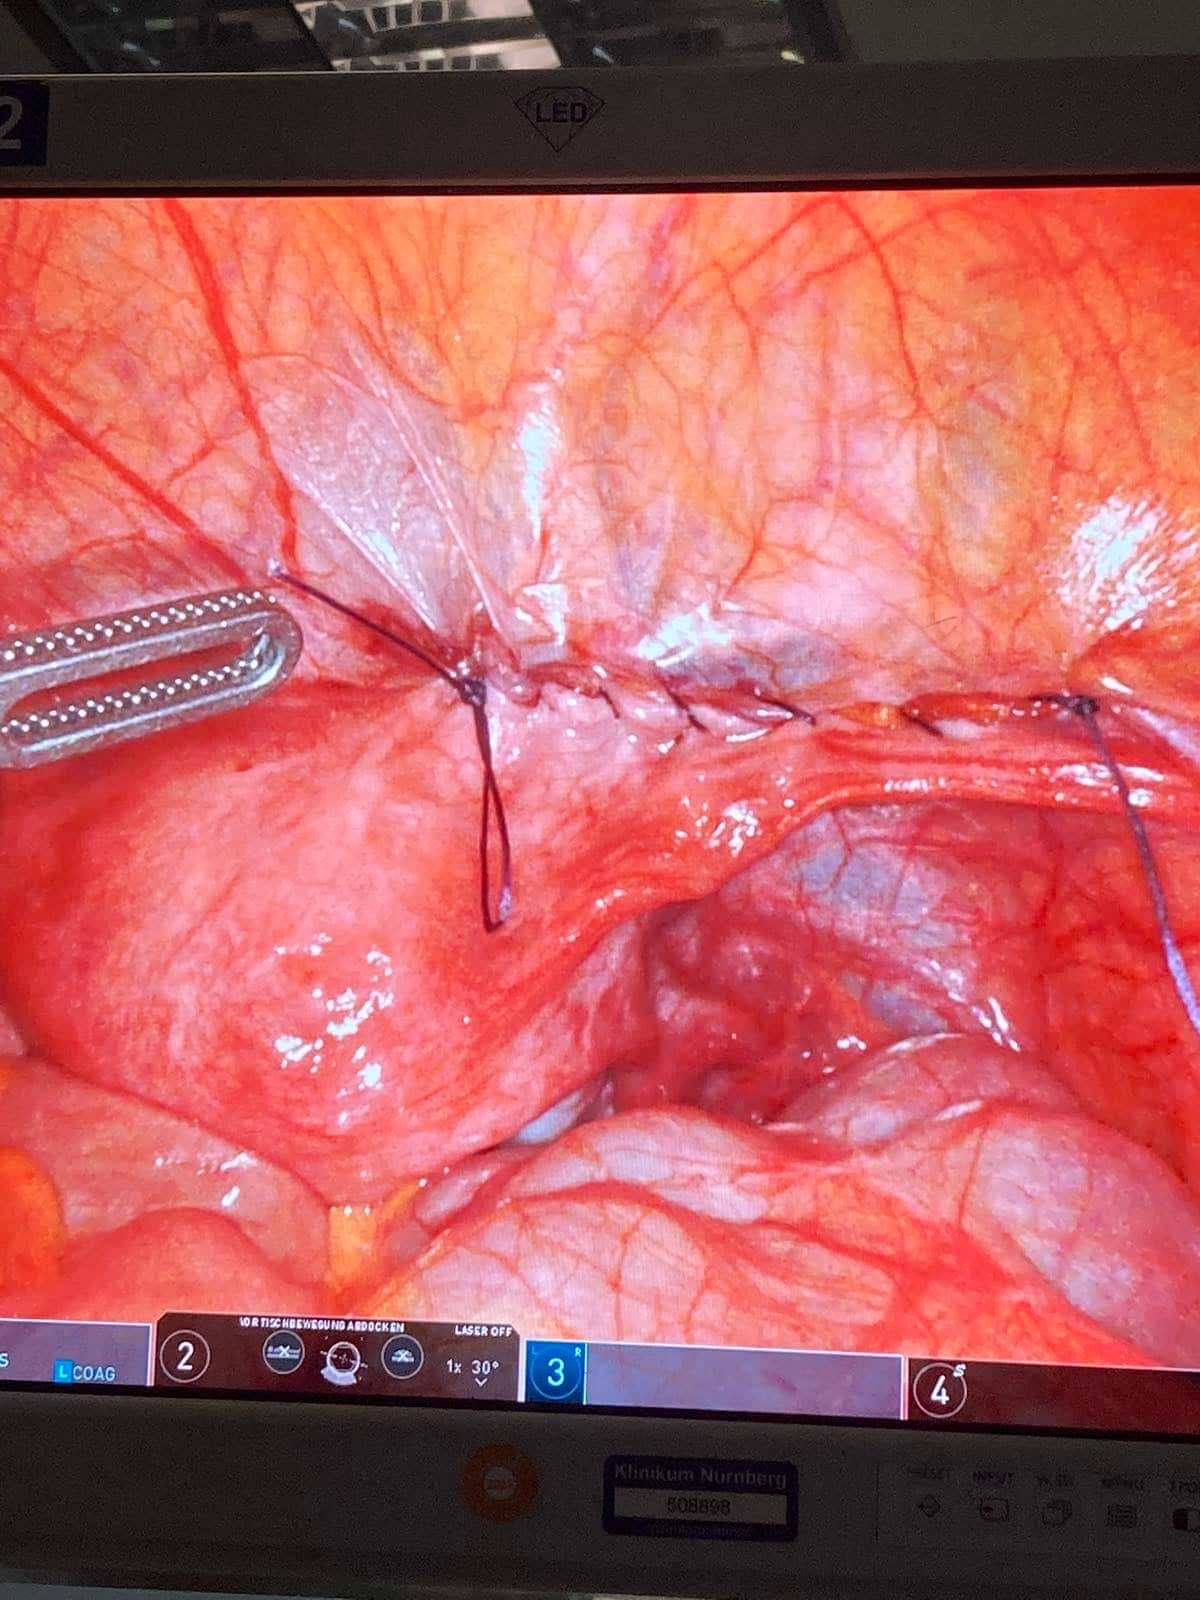

Μαιευτήρας Γυναικολόγος Βόλος Λάρισα | Ρομποτική Χειρουργική Da Vinci X